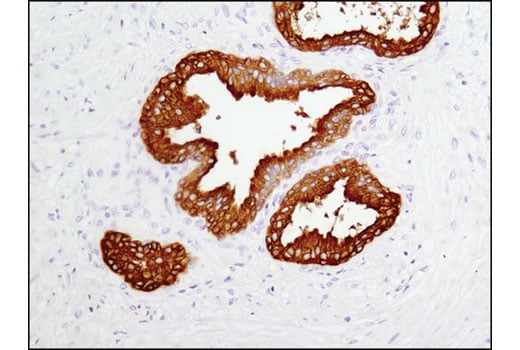

Immunohistochemical analysis of human prostate carcinoma using Prostatic Acid Phosphatase (D3Y5P) Rabbit mAb. Data were generated using the standard formulation of this product.

Immunohistochemistry Image 1: Prostatic Acid Phosphatase (D3Y5P) Rabbit Monoclonal Antibody (BSA and Azide Free)